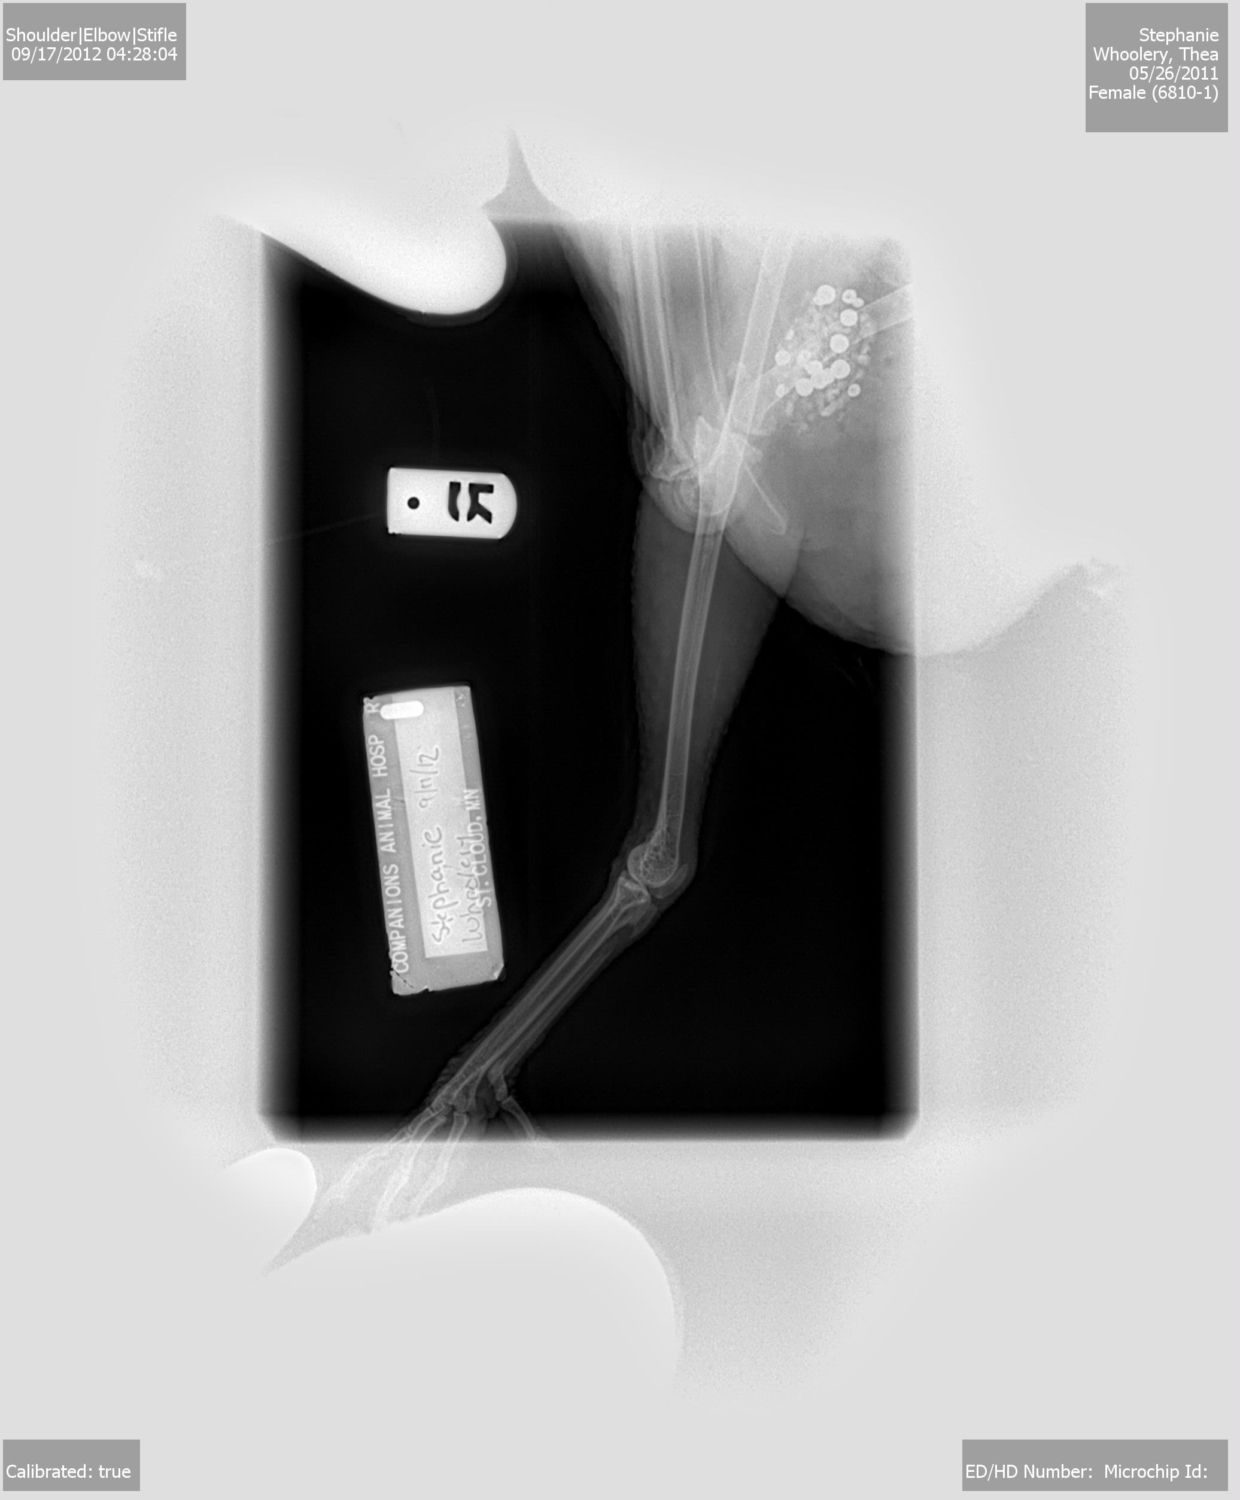

Took some xrays and everything looked good, not even swelling. We did a quick laser therapy session to hopefully help her out (was only like 20 bucks, whatever)

Aww such a sweet girl...she reminds me of my Chicklet. Neat X-rays. Did she say what those bead like things were inside her body...hehe

She asked me the same thing! She said that was the rocks in her gizzard and she wanted to know why the rocks or whatever are so perfect shaped. I thought that was sooo odd. I have no idea.